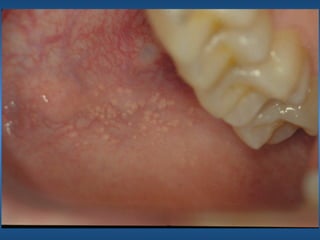

Grânulos de Fordyce

• Etiologia

• Características Clínicas

• Orientação Terapêutica